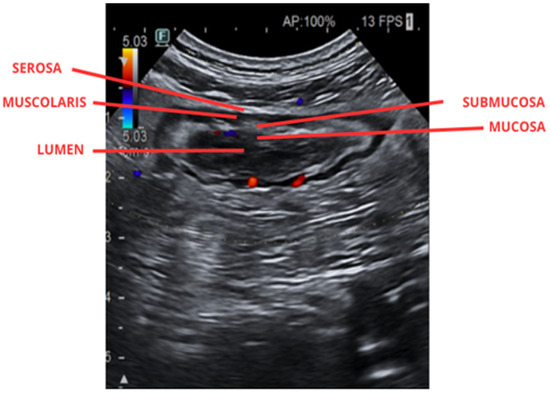

Integrating Intestinal Ultrasound in the Personalized Management of IBD

Personalized medicine is increasingly shaping the management of inflammatory bowel disease (IBD), with the goal of tailoring diagnostic and therapeutic strategies to individual patients. Intestinal ultrasound (IUS) has emerged as a pivotal, non-invasive, and repeatable tool for assessing disease activity, treatment response, and complications in both Crohn’s disease and ulcerative colitis. Beyond its role in routine monitoring, IUS enables real-time decision-making and facilitates tight control strategies, aligning with the principles of precision medicine. By combining morphological assessment with advanced techniques, such as contrast-enhanced ultrasound and elastography, IUS offers unique opportunities for risk stratification and individualized treatment planning. Moreover, its accessibility, safety, and patient acceptability make IUS particularly suited for longitudinal follow-up and early detection of therapeutic failure, thereby reducing the need for invasive procedures. This review discusses the integration of IUS into personalized IBD care pathways, highlighting current evidence, clinical applications, and future perspectives.